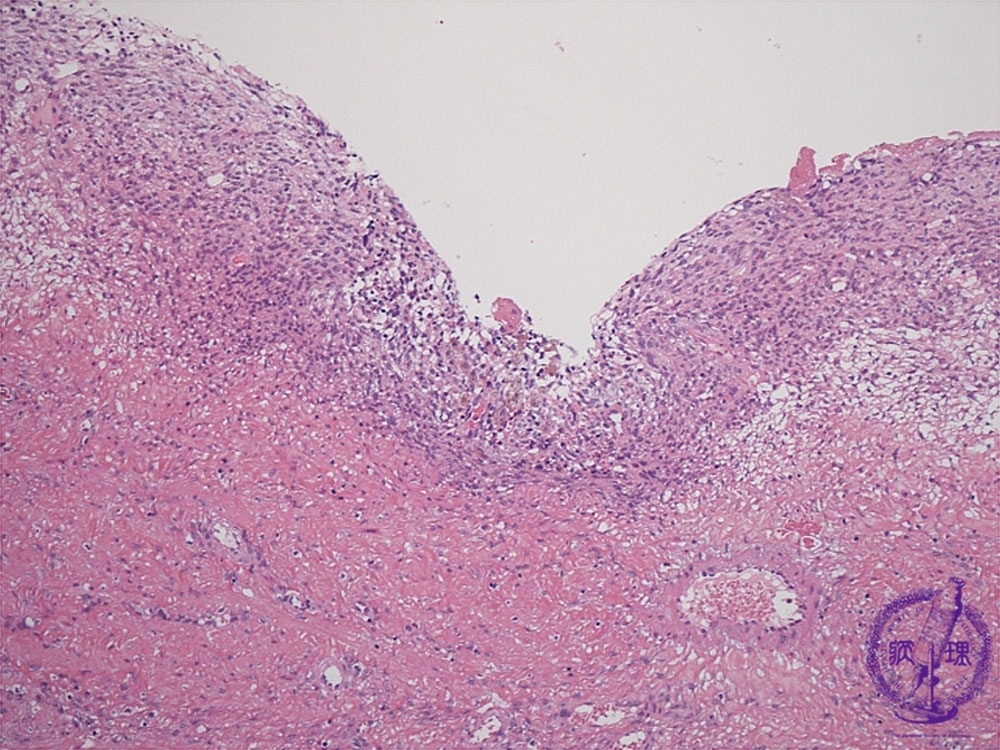

- 15.Female genital organs

- ★(2)Endometriosis

Histology (HE stain, low power): Ectopic endometrial tissue (stromal tissue), hemorrhage and hemosiderin-laden macrophages are apparent in the cyst wall (endometrial tissue: red dotted line, macrophages: yellow dotted line).

Click the image to see the enlarged image.